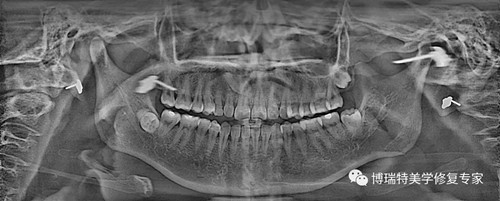

智能3D全景由外向内33张全景片观查

普通全景图(同一患者前牙区埋伏牙观察)